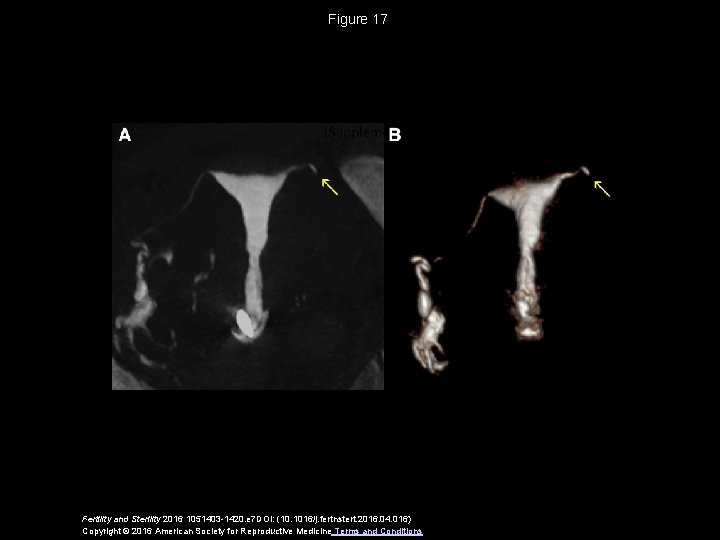

Figure 17 Fertility and Sterility 2016 1051403 -1420. e 7 DOI: (10. 1016/j. fertnstert. 2016. 04. 016) Copyright © 2016 American Society for Reproductive Medicine Terms and Conditions